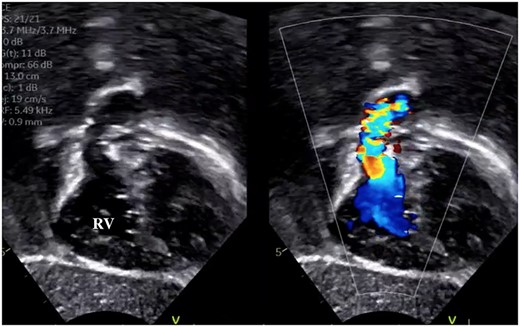

A male infant with TGA accompanied by Shaher Type 4 coronary anatomy underwent ASO at 5 days of age. Intraoperatively, the right ventricular outflow tract was injured during the RCA separation to obtain the mobilization and repaired using an autologous pericardial pledget, resulting in postoperative subvalvular PS. Follow-up evaluation showed relief of the subvalvular PS, but pulmonary valve stenosis, main pulmonary artery (PA) stenosis and right PA stenosis progressed because of the subvalvular jet. Transthoracic echocardiography showed a trans-right ventricle (RV) outflow peak velocity of 4.5 m/s, a systolic pressure gradient of 83 mmHg and a right ventricular fraction area change of 46.4% (Fig. 1). Cardiac catheterization showed a right ventricular pressure of 97 mmHg, a right ventricular/left ventricular pressure ratio of 0.99 and a systolic pressure gradient across the right ventricular outflow of 91 mmHg. The diameter of the pulmonary valve annulus was 6.1 mm (63.6%) (Fig. 2). Three-dimensional-computed tomography showed that the distance between the RCA and the tricuspid valve was 7 mm (Fig. 3).

Preoperative cardiac catheterization of the axial view (a) and sagittal view (b) showing PS, with the pulmonary valve annulus diameter of 6.7 mm.